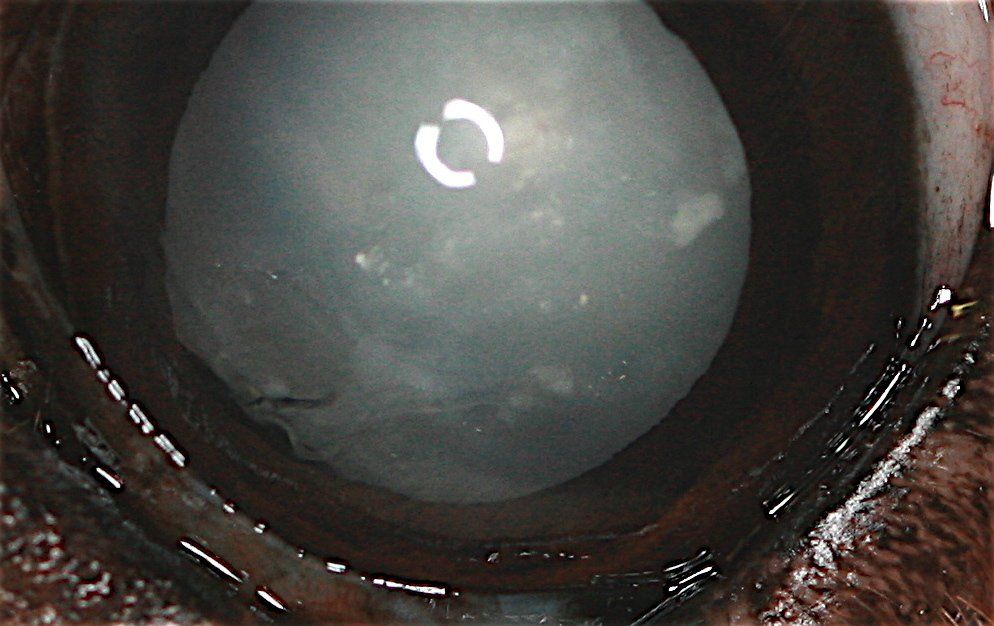

"Athos, male shih tzu, 11 years old, was presented for consultation for a corneal perforation dating back eight days following a fight with a cat. On the day of the consultation, Athos was shot (temperature 39.5°C) , no longer eating. The orbital region is very swollen, with an abscess under the palpebral and retrobulbar. The pain is intense and the ophthalmological examination is carried out under tranquilization."

Presence of a central perforation of the cornea with staphyloma, the whole being covered with a fibrin plug. Pus flows from a wound in the upper palpebral conjunctiva.

An intervention is performed under an operating microscope. The area is cleaned and disinfected. The fibrin plug is removed and reveals a staphyloma (passage of part of the iris in the corneal breach). In view of the age of the staphylop, a section of the herniated part of the iris is made. Anterior chamber flushing is performed. A viscoelastic substance Acrivet Biovisc® 1.2% is injected to restore ocular volume.

The infected appearance of the conjunctiva prevents us from performing a conjunctival flap to treat the corneal perforation.

A Vet BioSISt® prosthesis is placed and sutured using separate stitches with PDS 6/0.

Post-surgical treatment includes systemic antibiotic therapy and oral analgesics for 10 days. Locally, a drop of eye drops is instilled 3 times a day for 3 days.